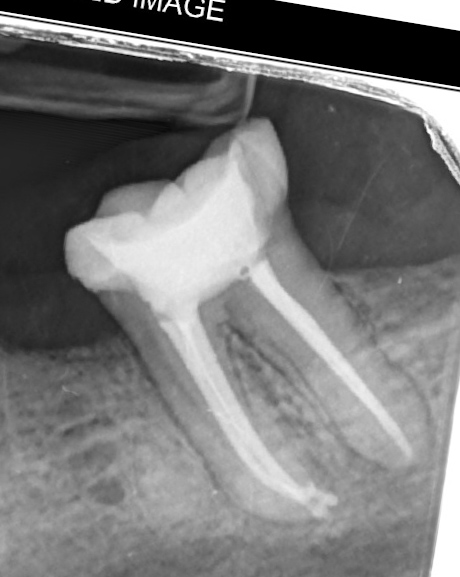

A patient complaining from severe pain in lower 7 had a previous root canal treatment, on examination tooth had severe response to percussion and root canal retreatment had to be done

🔹RC retreatment